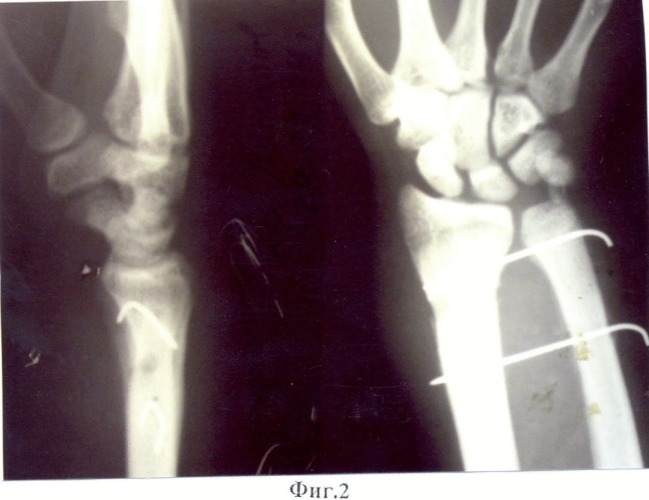

Радиоульнарный угол: строение и особенности лучевой кости